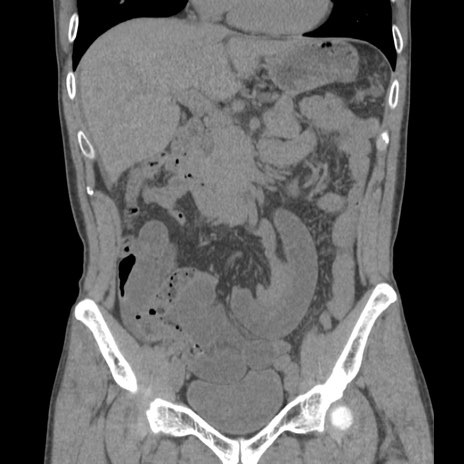

症例56 CT(冠状断像)

横断像